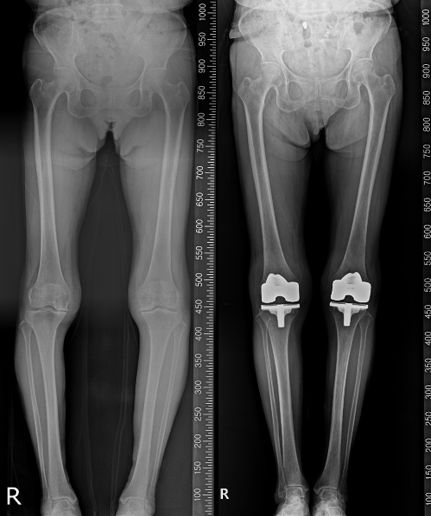

80세 여성 인공관절(pnk) 수술 전후. 연세사랑병원 제공

3단계 이상으로 심해지면 계단을 오르내리기가 불편해지고 결국에는 평지를 걷는 것조차 힘들게 된다. 관절염이 진행되면서 무릎 안쪽이 먼저 닳고 망가지게 되어 다리 모양이 '내반슬'이라고 하는 'O'자 형태로 변형되는 것이 일반적이다. 이처럼 3~4단계에 접어들면 관절이 절반 이상 마모돼 뼈와 뼈 사이가 달라붙어 통증과 염증이 매우 심하게 된다.

이때는 최후의 방법으로 인공관절 수술을 해야 한다. 인공관절 수술은 연골이 마모된 관절면을 다듬고 인체에 무해한 금속과 특수 합성물질로 인공관절을 삽입하는 수술이다.